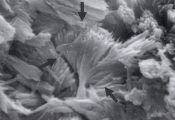

Рис. 29. Сканированная электронная микрофотография поверхности кальция оксалата, удаленного из мочевого пузыря 10-летнего кастрированного самца мальтеза. Обратите внимание на сульфадиазиновый кристалл веерообразной формы (увеличение Х 2,880).